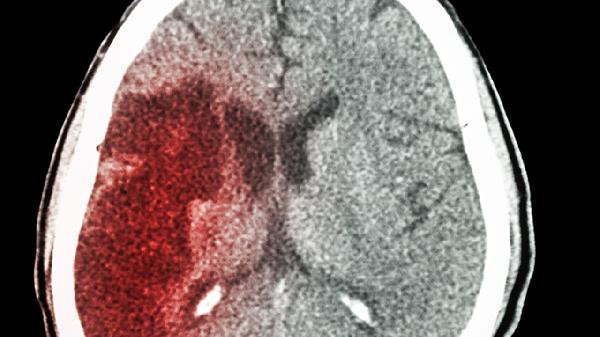

那天早上,父亲突然倒地,半边身子动弹不得,送到医院才知是中风。医生的一句话让我心如刀割:"其实,中风前身体会发出多次警.告,可惜很多人都忽略了。"翻看父亲的病历和日常记录,才发现那些被我们当作"小毛病"的信号,原本可以改写结局……